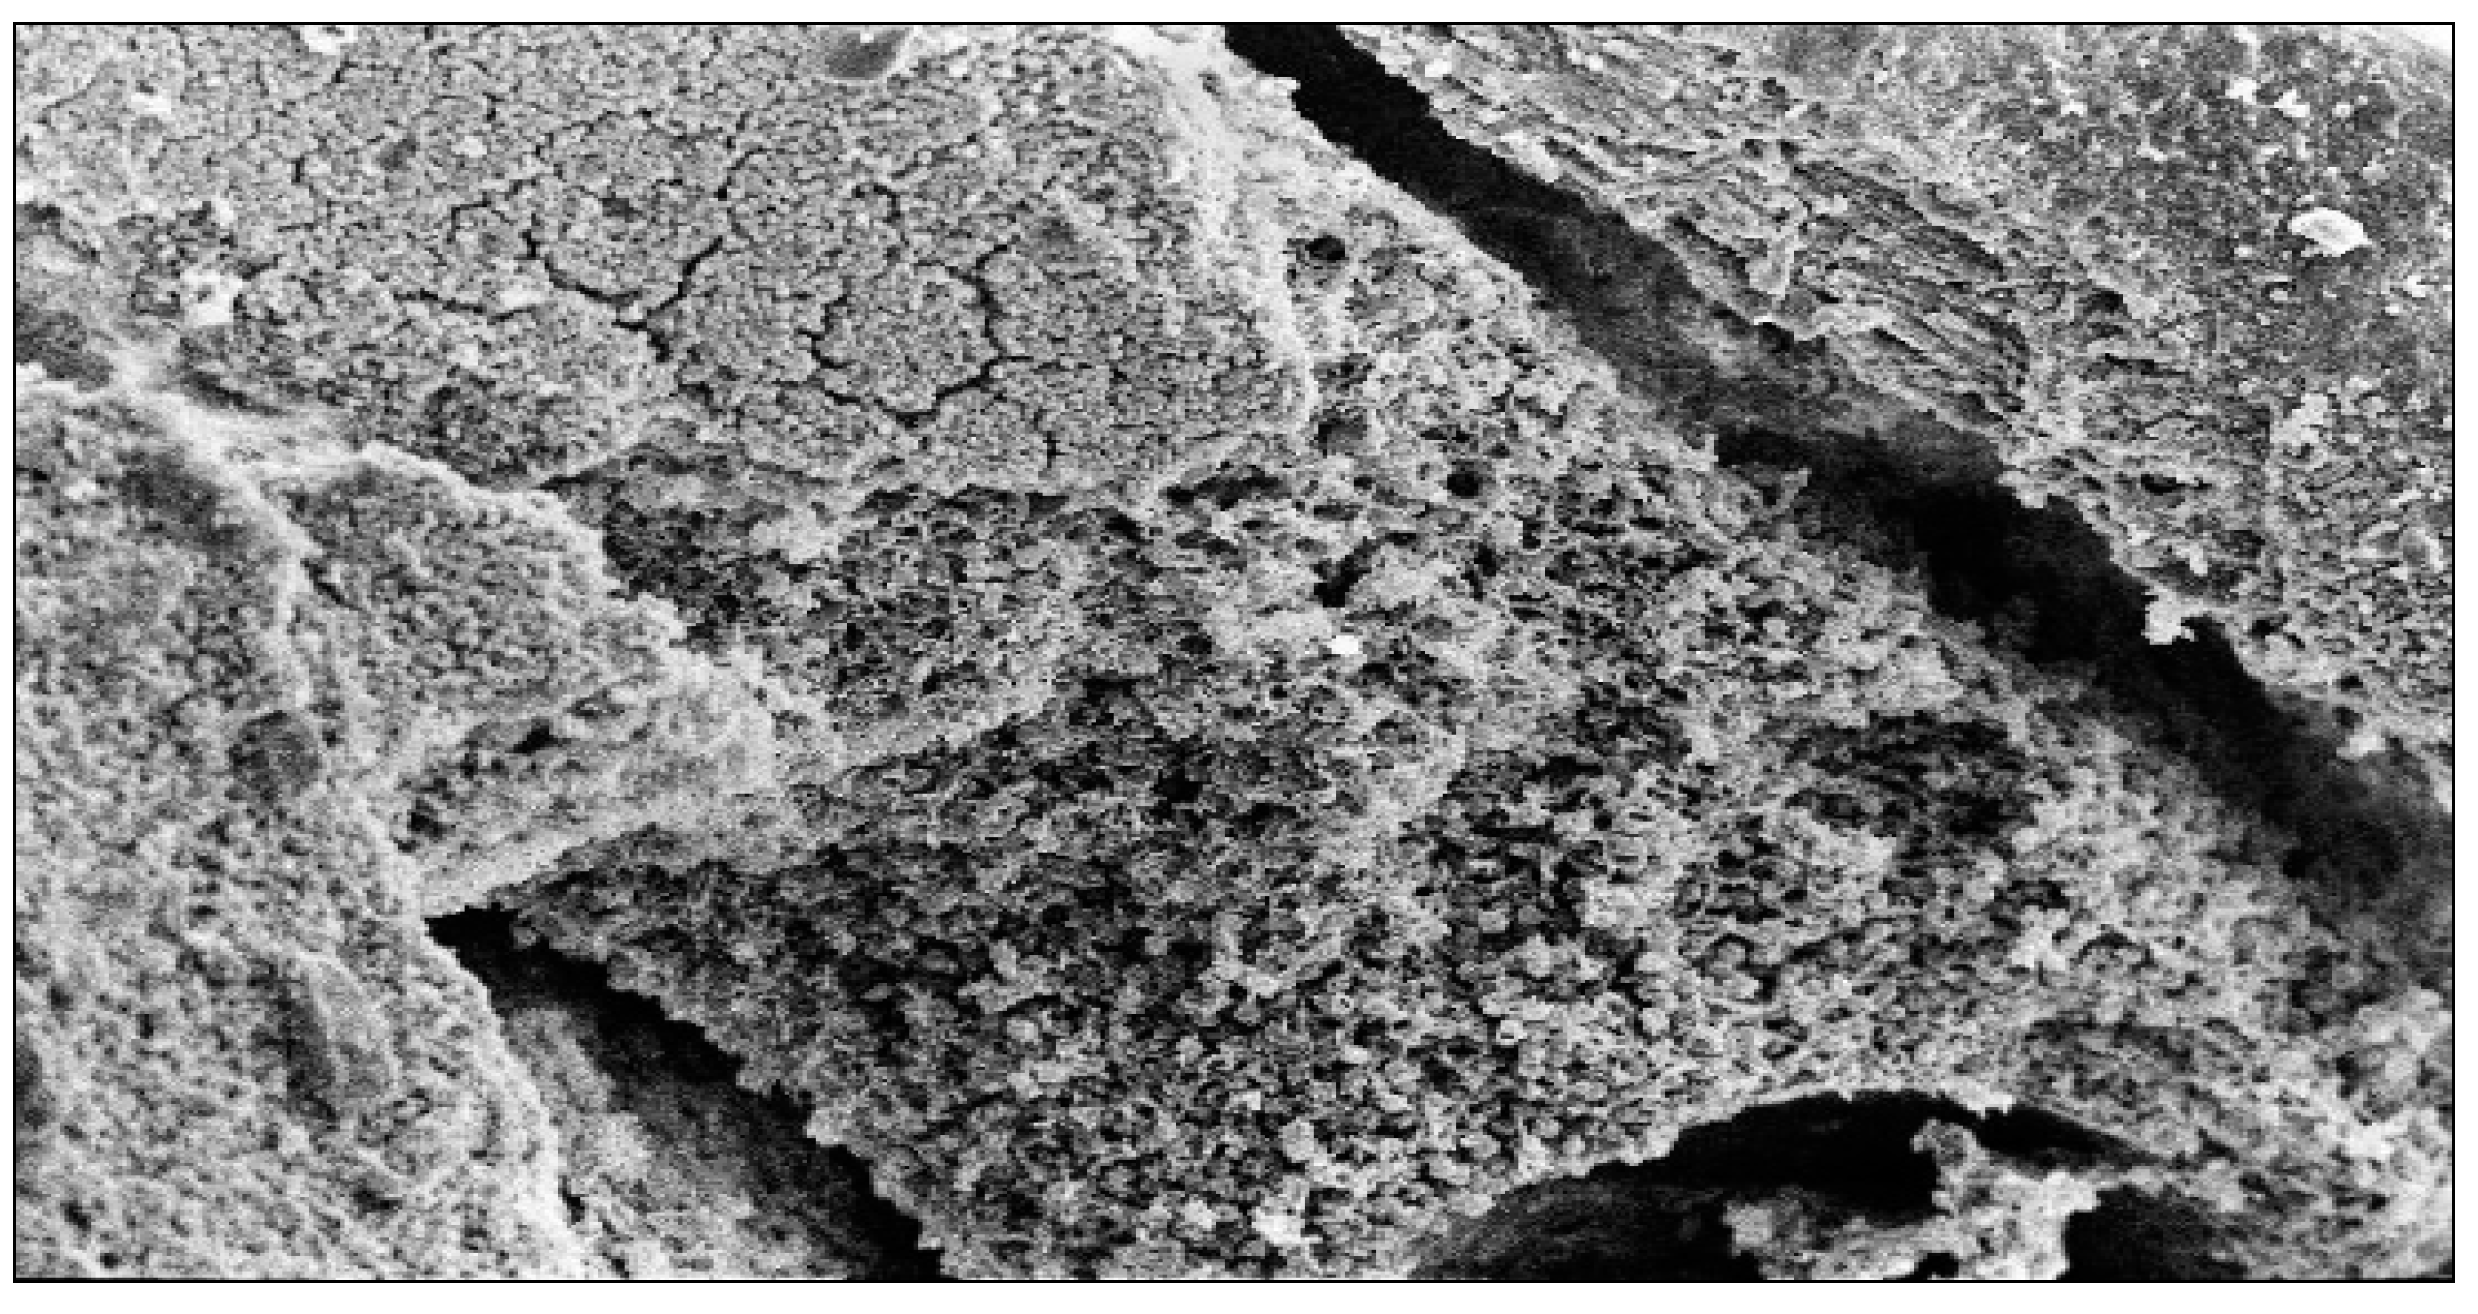

4.1.3. SEM Images with Ionic Gel and Iontophoric Application